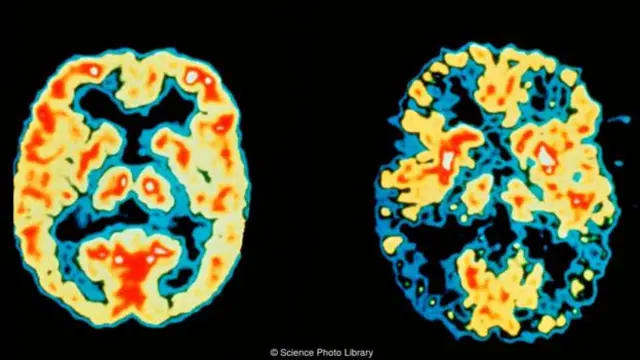

在过去的几年中,有新的科研成果表明睡眠对于减少与年龄有关的记忆丧失和轻度认知障碍和老年痴呆症都有重要的改善作用。动物研究表明,睡眠可以清除大脑中的废物,如淀粉样蛋白。淀粉样蛋白斑块的积累是阿尔茨海默痴呆症的病理特征之一。最近有关此类睡眠的“脑洗涤”功能的研究不断增加,人们对于从大脑中去除有毒物质的研究兴趣浓厚。